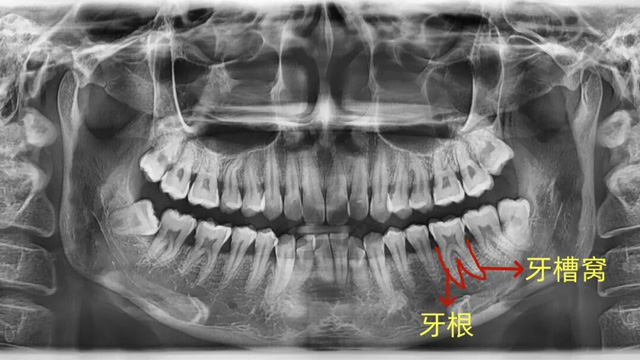

牙槽骨:牙齿的“土壤”

我们的牙根就像大树的根,深深扎根在牙槽骨里,每颗牙都有自己独立的“坑位”(牙槽窝),这是牙齿最核心的支撑。